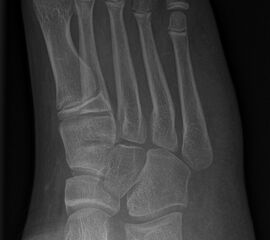

Abb. 18 a-b: Beispiel einer DMDO beim Hohlfuß d.p. (dorso-plantare) Ansicht (a) und schräge Ansicht (b).

DMMO/DMDO (Distale Minimalinvasive Metatarsale Osteotomie/Distale Minimalinvasive Diaphysäre Osteotomie)

Die Indikation für eine DMMO oder DMDO (Distale Minimalinvasive Metatarsale Osteotomie/Distale Minimalinvasive Diaphysäre Osteotomie) beim Kind mit wachsendem Skelett ist nicht die klassische Metatarsalgie des Erwachsenen. In der Kinderorthopädie kann eine gute Indikation für die DMMO oder für eine DMDO der Ballen-Hohl-Fuß mit Metatarsalgie sein. Wird z. B. bei einer frühen Hohlfußkorrektur das Metatarsale I für eine bessere Rückfußeinstellung extendiert und zur Aufhebung der Extensorensubstitution die Sehne des M. tibialis posterior transferiert, kann sich im Verlauf eine Dysbalance der Metatarsalia entwickeln und eine Metatarsalgie unter II-IV auftreten. Mit einer DMDO werden die Köpfchen II-IV effektiv angehoben und die Beschwerden gebessert (Abb. 17 und 18).